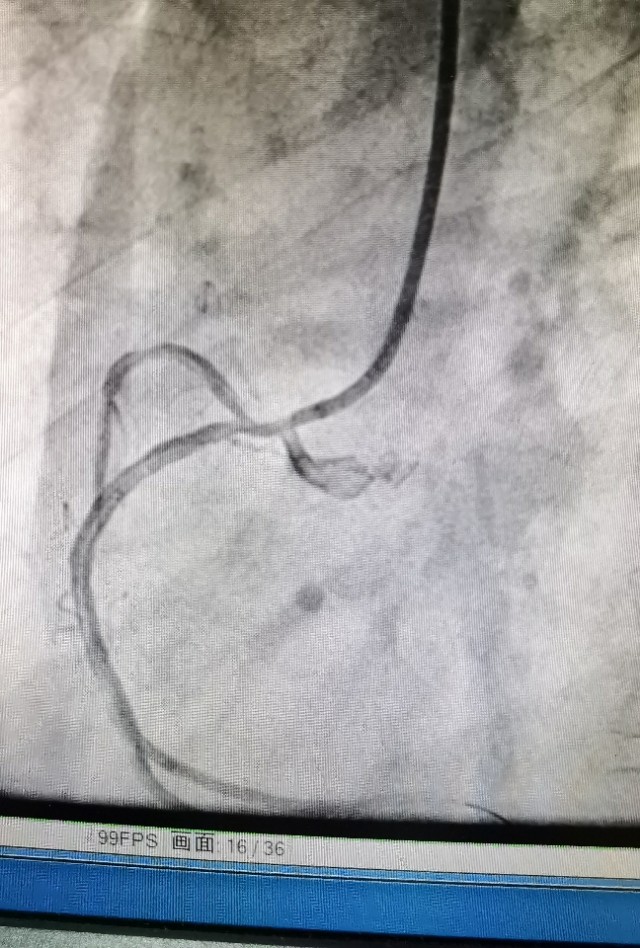

病例1 发现开口病变,精准植入支架

中年女性,劳力性胸闷多年,造影发现Guilding“嵌顿”现象,OCT发现开口严重狭窄,药物球囊治疗后效果良好。